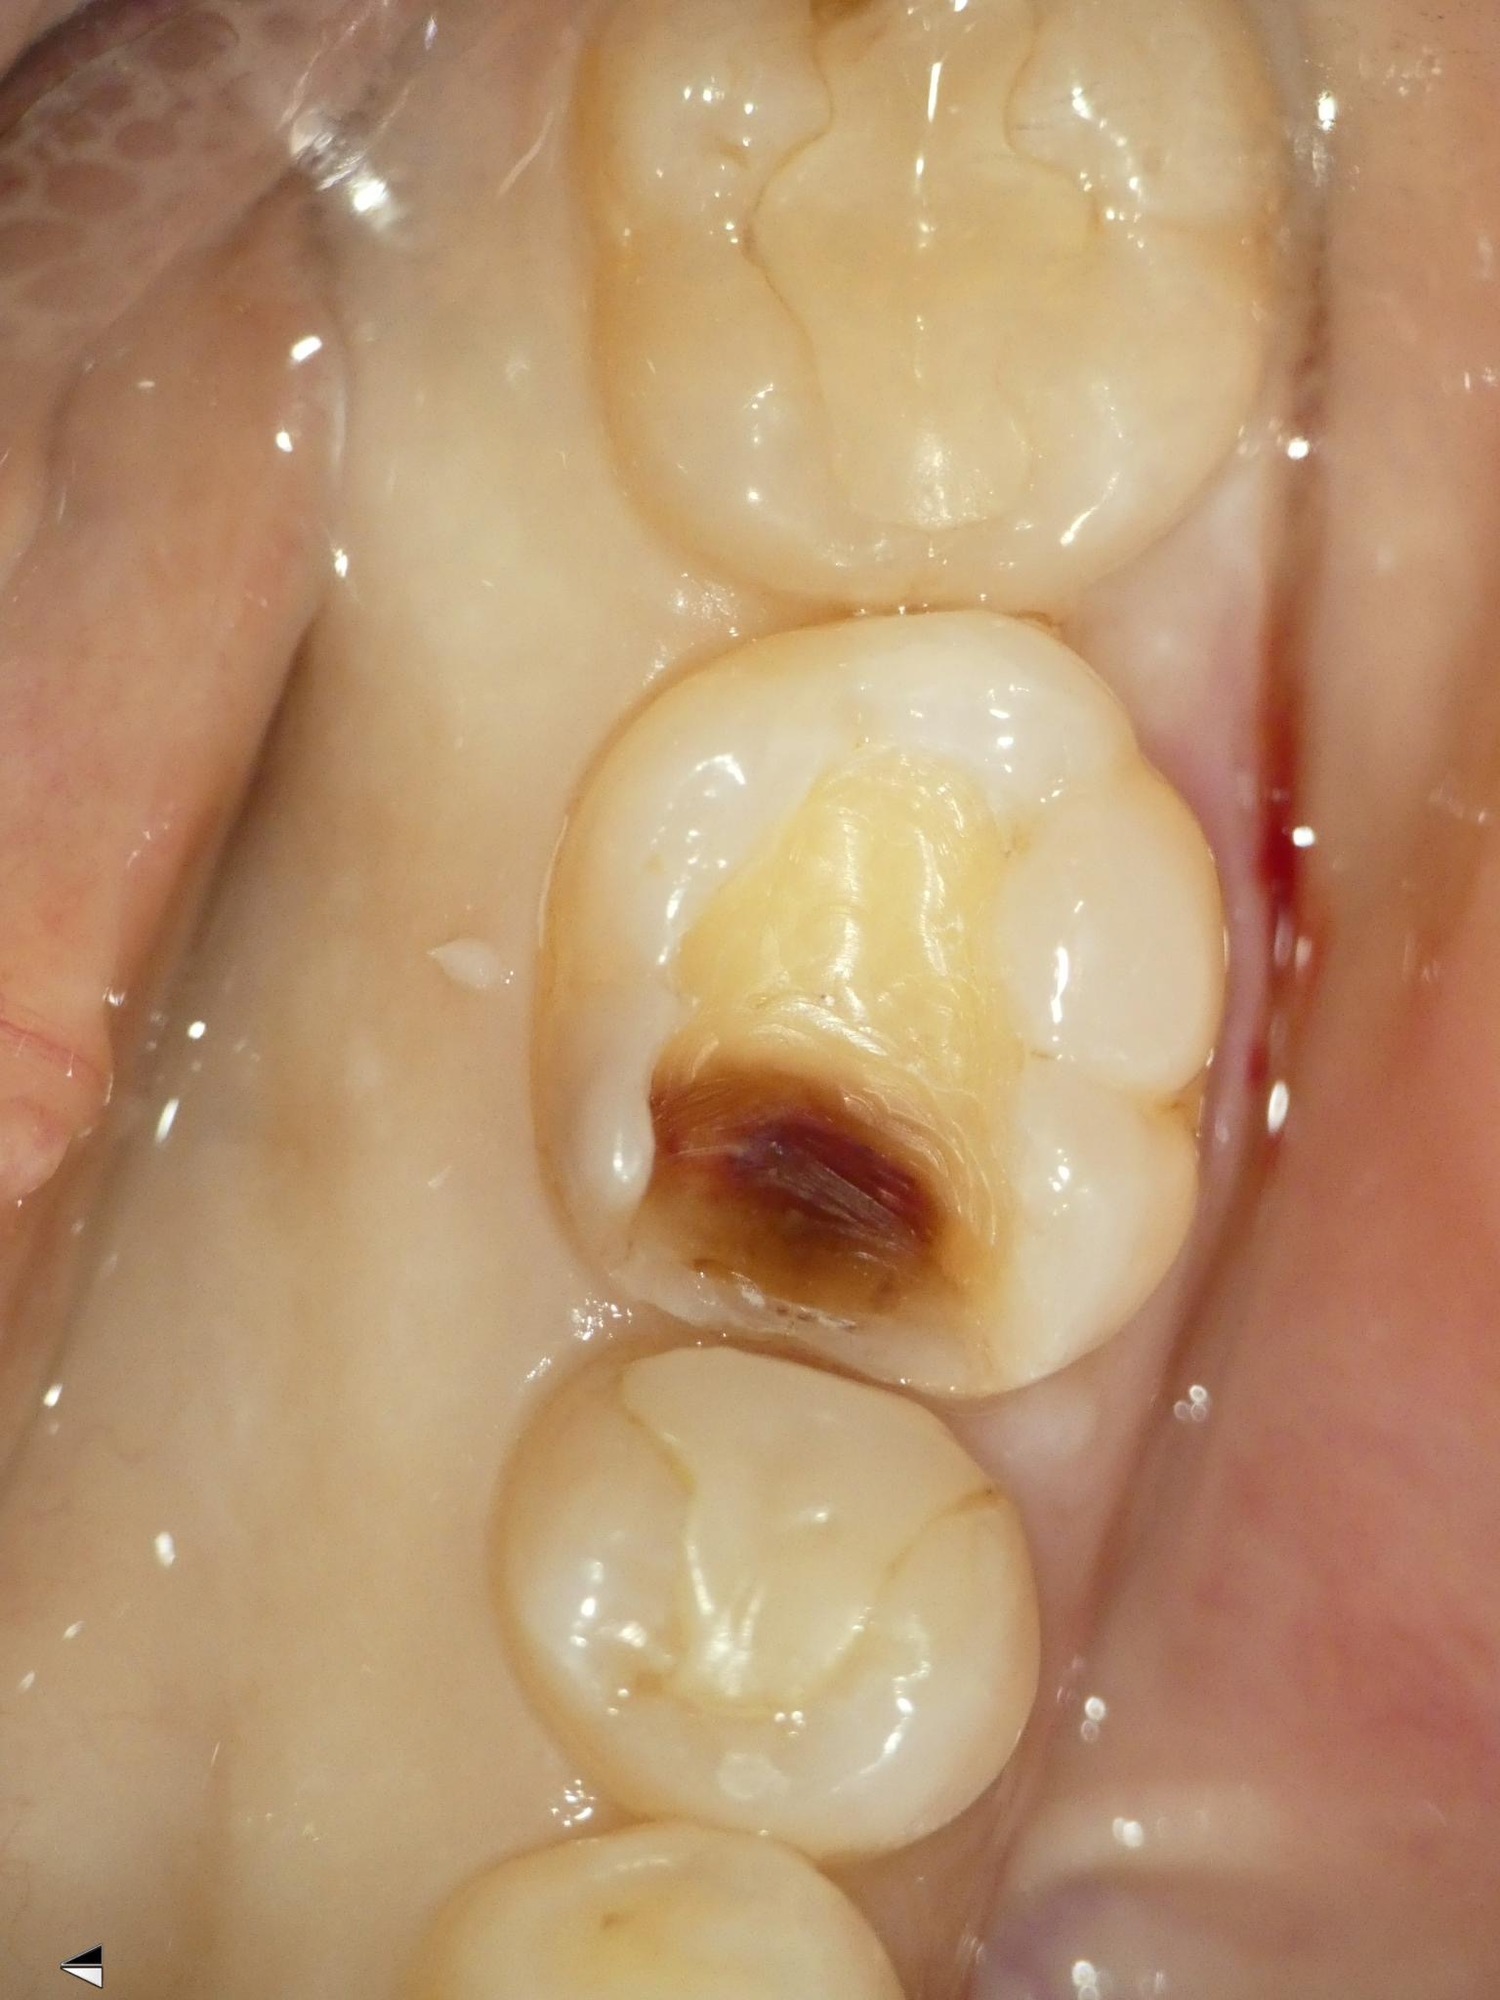

左下の前から6番の歯の虫歯治療の症例を紹介させていただきます。

こちらは保険診療で、コンポジットレジン修復で治療をしております。